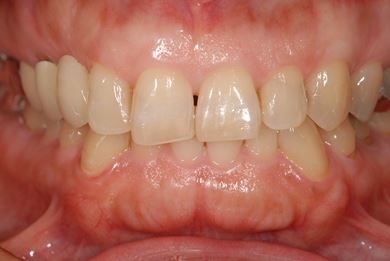

治療後

• 治療後